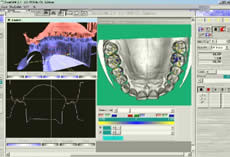

Introducción.- En oclusión, existen varios campos de aplicación básica para la digitalización. Hablamos, preferentemente, de la digitali- zación tridimensional. Recordemos que esta palabra es sinónimo de medición y –como tal- auxilio en esta rama odontológica tan necesitada de precisión. La digitalización tridimensional consistirá en el registro de la posición espacial, de un finito número de puntos, determinando sus coordenadas -x,y,z-. A menor distancia entre cada punto se conseguirá como resultado un objeto virtual con mayor detalle, coincidente con el real. Con cada triada se podrá formar una superficie, que continuada con la generada por el resto de la malla de puntos, completarán la forma del objeto. Este es el origen de donde partimos para establecer el concepto básico de las revolucionarias aplicaciones 3D. Se parte así del denominado escaneado tridimensional: Escaneado Superficial de un objeto real -> “Nube de Puntos” -> “Malla de Alambre” -> Superficie del Objeto Virtual. Con los modelos dentarios, impresiones o registros de oclusión, virtuales (en la pantalla del ordenador), realizaremos ahora, mediante un programa informático, la manipulación simulada, mediante computadora, para la realización del estudio y diseño de la oclusión. La Oclusión Computarizada (OC) –dentro de la más amplia Odontología Computarizada- comprende, hoy, fundamentalmente, tres fines: 1º)- El Estudio, Diagnóstico y Plan de Tratamiento Asistidos por Ordenador. 2º)- El Encerado Computarizado. (Por RP –Rapid Prototyping-, Prototipado Rápido, o por CAM –Computer Assisted or Aided Machining or Manufacturing-, Maquinado Asistido o Ayudado por Computador). 3º)- La Restauración y Confección de Prótesis Computarizada. (Por CAD-CAM, -Computer Assisted Design – Computer Assisted Manufacturing-, Diseño y Fabricación Asistidas por Computador). La Odontología Computarizada tiene entre sus numerosas secciones, ésta de oclusión, considerada primordial en el trabajo clínico habitual, desde la que nos relacionamos con la ortodoncia, cirugía implantológica, tecnología protésica y prostodoncia. Cada uno de los citados fines de la OC necesita partir de un escaneado tridimensional de los objetos a tratar: elementos del sistema dentario (arcadas) –de forma directa, en la misma boca del paciente-, o modelos dentales obtenidos por una impresión material de éstas y su posterior escaneado –o forma indirecta, fuera de la boca del paciente-. El escaneado se puede realizar con variados dispositivos, resultando procedimientos de distintos tipos y con diferentes características, clasificados simplificadamente como: A) Escaneado de contacto, háptico: B) Escaneado sin contacto: Tomando una imagen del objeto, marcado por líneas o cuadrículas luminosas proyectadas sobre su superficie, que se deforman con ella, analizándose luego digitalmente. El escaner se considera aquí un analizador trigonométrico del objeto, que registra su imagen, marcada mediante un rayado por luz –normalmente láser- (que permite, mediante software, obtener las coordenadas espaciales de multitud de puntos, que son agrupados en unidades de tres, constituyendo los vértices de una superficie triangular, que sumándose a las vecinas, llegarán a representar la envuelta completa del objeto y así su forma volumétrica o tridimensional). C) Combinado. Externo e Interno. Los escáneres suelen resultar, actualmente, poco económicos, y aunque van decreciendo en coste, están –para estas fechas- en un nivel que suele partir como mínimo de los 8.000 euros; siempre dependiendo del procedimiento de registro empleado, tamaño y precisión del escaneado. Existen: A) aparatos integrados en sistemas dentales, desarrollados específicamente para nuestro campo, de comprobada eficacia y de alto coste económico; B) dispositivos de uso general, aplicables a los propósitos de la odontología, de complicada adaptación pero de muy bajo coste relativo; C) múltiples posibilidades para la construcción de un escaner propio, casero y económico, que pueda, con suficiente experiencia, llegar a funcionar para uso profesional, gracias a la existencia de suficiente información de la tecnología empleada, ampliamente divulgada y de fácil desarrollo; útiles para fines diagnósticos. En oclusión necesitamos el 3D, pero también el 4D. Sumamos aquí a las tres coordenadas espaciales de cada punto del objeto, otra más, la cuarta dimensión: el tiempo. Dado que un objeto móvil, lo es por la temporalidad de sus posiciones en el espacio. Así se registrarán y analizarán digitalmente los movimientos mandibulares para conseguir la articulación y reproducción de la función masticatoria. Para esto se han aplicado determinados registros, mediante sensores de posición o por receptores de actividad muscular, como los electromiógrafos, o el más específico articulador virtual, del que se encuentran diferentes productos de software, englobados –como complemento necesario- en los programas que acompañan a los distintos sistemas de cad-cam dental. Desde el escaneado, o transformación u obtención del objeto real en cuerpo 3D, numérico, adquirido para ser estudiado y manipulado de forma digital, virtual, en el computador, continuamos con otras vías, ahora posibles, de enorme potencial, desde el estudio y planificación a la fabricación protésica. Así van a ser expuestas a continuación: A) La planificación; B) el encerado; y C) la fabricación. A) -Estudio, Diagnóstico y Plan de Tratamiento Asistidos por Ordenador. La planificación de la rehabilitación oclusal, puede iniciarse: A-1) Por Registro Estático Morfológico Computarizado, del aparato estomatognático y sistema dentario. Que puede realizarse: I) A partir de Escaneado Extraoral. I-a) Escaneado Volumétrico (CT–tomografía computarizada-) (O mejor, CBCT –tomografía computarizada de haz cónico-, de menor radiación y coste, con aparatos diseñados específicamente para uso dento-máxilo-facial ). I-b) Escaneado Superficial –de los modelos de estudio- y Registros Oclusales-. II) A partir de Escaneado Intraoral. II-a) Escaneado Volumétrico (CT local, o CBCT local, que se están desarrollando para aplicación retroalveolar). II-b) Escaneado Superficial –de las caras oclusales del sistema dentario-. A-2) Por Registro (Estático Morfológico Computarizado) de Huellas de Oclusión (o Registros Oclusales), para análisis de contactos intermaxilares, estáticos -y menos o indirectamente los movimientos mandibulares-. Mediante escaneado superficial de registros, sus modelos 3D, y combinación o no, con el Papel de Articular Electrónico (T-Scan). A-3) Por Registro Dinámico Funcional (fisiológico) Computarizado: I) Registro Computarizado (Integrado) de los Movimientos Mandibulares –electropantográfico o cinematográfico-. Por sensores o marcadores de posición. II) Registro Computarizado (Integrado) de la Función Muscular –electromiográfico-. A-4) Por Integración Informática de varios de los Registros citados. B) -Encerado Computarizado. Es el modelado o diseño virtual en la pantalla del ordenador y su realización en material de patronaje (como la cera u otro de similar; económico, modificable, transformable y rápido), que puede realizarse por: B-1) Por RP –prototipado aditivo- o B-2) por CAM –maquinado sustractivo-. Como pensamos en el concepto clásico, la realización de un encerado diagnóstico es clave para una rehabilitación oclusal correcta. Además el encerado servirá para la confección de: a) una posible férula radiológica y quirúrgica, b) una referencia para el tallado, la prótesis o rehabilitación temporal y el patrón para la definitiva. Se llevará a cabo, en dos etapas: 1ª) Etapa de creación del patrón. Elaboración virtual en la pantalla del ordenador. Necesitando el software apropiado, CAD. 2ª) Etapa de confección. Elaboración Real, mediante RP o CAM. 1ª) La etapa de creación virtual del patrón en la pantalla del ordenador, mediante un programa informático de diseño y manejo de objetos tridimensionales, (siempre partiendo de un registro previo, como el escaneado de los modelos), puede facilitarse con varias herramientas para: -Elaboración Virtual por Adición. 2ª) La etapa de confección, o elaboración real, mediante RP o CAM. -Confección por RP (Rapid Prototyping) –Prototipado Rápido-, de adición o construcción capa a capa, añadiendo una sustancia que se endurece, aumentando su nivel en superficie. La elaboración real por adición, es posible en un variado –pero limitado- tipo de materiales. -Confección por CAM (Computer Aided Machining) –Maquinado o Tallado Asistido por Ordenador-, de eliminación de sustancia o esculpido en un bloque sólido. La elaboración real por sustracción, es posible en un numeroso -y casi ilimitado- tipo de materiales. Existen gran cantidad de dispositivos que consiguen la fabricación y consecución física de un encerado real, a partir de su elaboración virtual, desde un escaneado y su diseño computarizado. Todos los sistemas denominados de cad-cam dental, en general, aunque no estén espe- cialmente dispuestos para ello, pueden dedicarse a este propósito; simplemente colocando un material de patronaje, como la cera, en lugar del material con el que se constituirá la prótesis definitiva. Pero, existen –también- sistemas espe- cialmente configurados para el trabajo en material de diseño, normalmente: ceras, resinas o compuestos, es lo que se denomina prototipado rápido (rapid prototyping). En la industria general, la fabricación de cualquier objeto en serie, requiere de estos procedimientos en las primeras etapas de elaboración para su producción. La más económica y reducida Impresora 3D o Sistema de Prototipado Rápido, que puede confeccionarnos unos maxilares, a partir de la tomografía, o un encerado diagnóstico, según el software disponible. Su precio actual 45.000 Euros. C) -Restauración y Confección de Prótesis Computarizada. (Por CAD-CAM). Es el modelado o diseño virtual en la pantalla del ordenador y su realización en material definitivo (como porcelana, titanio, aleación preciosa, u otro similar); poco económico, difícilmente o no modificable, ni transformable y que requiere de un tiempo adecuado, mucho mayor que el requerido para la confección del patrón de material plástico. Esto puede realizarse por numerosos dispositivos. Existen gran variedad de sistemas para el diseño y confección de restauraciones y prótesis. Son los denominados gene- ralmente SISTEMAS DE CAD-CAM DEN- TAL (Dental Cad-Cam System): (Entre estos sistemas encontramos los que también pueden planificar el tratamiento restaurativo y realizar el encerado diagnóstico con diseño y confección de un patrón oclusal; como hemos referido antes). Históricamente estos sistemas comenzaron con la década de los setenta -en 1971, con el Holodontography-Altschuler System-, y con el Sopha System de Duret, progresando enormemente hasta comienzos de los noventa. Durante esos veinte años, se potenció su desarrollo con el siguiente hito histórico que los encumbró, en su segunda década, por la aparición de los principales impulsores del cad-cam clínico comercializable -Mörmann y Brandestini, en 1981-, denominado Sistema Cerec. También se establecieron los principios de estos dispositivos con el DCS Dental System, el CAP System, el Minnesota-Rekow System, el Nissan Cad/Cam System, Automill y Microdenta System. El culmen del progreso se alcanzó a mediados de los noventa, con sistemas ampliamente comercializados y evolucionados hasta hoy: Procera, DCS Dental, o Cicero. En los siguientes diez años, se continuó perfeccionando los sistemas citados; hubo algunos sistemas no comerciales o de escasa difusión, o distribuidos moderadamente; repre- sentando un período hasta el 2000, con una pequeña depresión, en los años medios, por el declive en la extensión de estos productos, en relación al extraordinario futuro que se les auguraba, motivada por el alto coste de los equipos y las limitaciones en su potencia digital, en el que –aún y así- aparecieron sistemas como: Belledent, Cadim, Dentscan, CCD System, Cynovad, Digident-Girrbach, Decim y Etkon. La segunda revolución para la odontología por cad-cam se produjo con el comienzo del siglo. Ampliándose enormemente la cantidad de sistemas y alentándose una explosión del trabajo digital en odontología, con: Cercon-Degussa, Lava-3M-Espe, Cad-Esthetics System-Ivoclar, DDS, GC-Dental, Everest-Kavo y Bego. En estos momentos el futuro de la odontología se encuentra inexorablemente unido a estos aparatos. Para el clínico o el laboratorio dental es hoy imprescindible contar con ellos. Siguen nuevas apariciones, como el sistema Hint-Els, o el Evolution-4D, similar al Cerec, que fue el pionero, pero que todavía, a la fecha, se mantiene como el más versátil, modulable y práctico, con progresos como el facilitado trabajo de diseño tridimensional o el nuevo escaneado extraoral independiente. Los sistemas de cad-cam, están integrados por: un escaner que digitaliza el objeto dental, un ordenador con el software adecuado para el diseño virtual, y una máquina de tallado para la fabricación del objeto diseñado en un material determinado. Una relación actualizada, de gran número de los sistemas existentes se encuentra en “Aktuelle CAD/CAM Systeme”, en http://www.tu-dresden.de/medprothetik/computerzahn/CAD-CAM-Systeme.htm Factores clave en la Oclusión Computarizada-. La digitalización del estudio, diagnóstico y tratamiento de la oclusión, como la construcción o restauración de un sistema dentario óptimo para la correcta función masticatoria del aparato estomatognático, pretende facilitar y generalizar la excelencia en el trabajo clínico. Es una aplicación de preferencia informática porque pueden manejarse gran cantidad de datos, mediciones, relaciones geométricas, unidas a la tridimensionalidad y la movilidad de sus elementos, de una forma racional, lógica y científicamente fundamentada, aún partiendo de concepciones filosóficas o criterios sujetos a distintas escuelas de oclusodoncia. La digitalización de la oclusión pude llevar- nos a despejar supuestos sin evidencia científica, de la que adolece sectorialmente nuestro arte. Tenemos suficientes fórmulas, reglas y relaciones numéricas, aportadas por numerosos autores, que tienen que se recopiladas y que pueden así ser aplicadas. Yá que la digitalización recoge todos los datos métricos y posicionales (coordenadas de cada punto, con su x,y,z), del sistema dentario, se pueden establecer fórmulas matemáticas para que -siendo la z la determinante de la altura de un punto en el espacio-: una z máxima, de una pieza mandibular, esté más o menos próxima a una z mínima de una pieza maxilar; que un punto (de cúspide) -con una determinada x,y- maxilar, coincida con otro –con la misma x,y- mandibular, pero con distintas aunque casi idénticas z, dándose el contacto oclusal. Y de esta forma, con sucesivas relaciones (matemáticas) se construiría una oclusión tendente a la excelencia; matemáticamente desarrollada. Así podría confeccionarse, automáticamente, una oclusión geométrica, dando, por ejemplo, solamente: la posición base de cada pieza, la x,y de las cúspides de una hemiarcada, y la altura de su plano oclusal, y automáticamente se generarían las cúspides agonistas y antagonistas, y la morfología dental completa de ambas arcadas. Se tendrían que añadir los datos correspondientes a los dientes anteriores, a las ATMs y las fórmulas de relación de las pendientes. Distintos autores han desarrollado relaciones métricas en oclusión. Algunos han simplificado el proceso, como partida, para ir añadiendo variantes; así, pueden usarse valores standard, normales, del ángulo cuspídeo para fabricar la morfología oclusal en CAD/CAM, -cuando la creación del esquema oclusal es de novo-, según Hobo y Takayama; y el uso de varios valores fijos de partida, universalmente aceptados, en lugar de la medida directa de la pendiente condilar es, según los mismos autores, muy importante en el desarrollo extenso de los sistemas de CAD/CAM. Así, el procedimiento de «twin-stage» propuesto por estos autores, en su libro “Oral Rehabilitation”, proporciona una solución en la producción de una oclusión dinámica tridimensional para el CAD/CAM. Otra técnica, consiste en el encerado virtual, mediante un modelado CAM, siguiendo las etapas de Shillimburg, o Kuwata, elaborando paso a paso la morfología oclusal, orientada a su enfrentamiento con el antagonista, encaminando los volúmenes cuspídeos como en el encerado progresivo clásico, gota a gota. Se realizaría su construcción virtual en la pantalla del ordenador, pudiendo estar facilitada su manipulación, mediante “espátulas de encerado virtual”, utilizando los digitalizadores de brazo articulado, con los que se pueden disponer los volúmenes necesarios, en la posición espacial que se desee. No obstante, el modelado dental se puede realizar siempre, aunque sea a través del clásico ratón del ordenador, de forma virtual, con la imagen tridimensional en la pantalla, utilizando diferentes procedimientos, con el software adecuado: A) Automático, a partir de las reglas dentométricas, odontométricas y cefalométricas, relacionadas con la gnatología, tomando previamente los valores claves necesarios del paciente. B) Mediante diseño de la anatomía con trazado de los perfiles, líneas y curvas, que van a definir las superficies dentales. Trabajando bidimensionalmente, en base a cortes de la estructura a construir, que manipulada variando sus dos dimensiones, va a corresponderse con la morfología dental tridimensional, al establecerse un área de influencia y cambio en los cortes vecinos, y así alterándose el volumen dental completo. Este era el procedimiento de variación anatómica utilizado, durante dos décadas con el Sistema Cerec (el Cerec 1, Cerec 2 y Cerec 3), hasta la llegada del Cerec 3D. C) Mediante copiado de la cara oclusal ideal, realizada previamente en cera u otro material real, del diente, su registro oclusal o su antagonista, en el concepto original del Sistema CEREC, de construcción oclusal mediante Correlación –copiando un encerado previo- o Función –correspondiendo automáticamente a la cara oclusal del antagonista-. D) Mediante selección de dientes, individuales o en grupo (incisivos, caninos, premolares, molares, arcadas, hemiarcadas, sistema dentario, maxilares o mandibulares), de entre un grupo de archivos de modelos dentales tridimensionales virtuales, como una librería de objetos 3D. Como en la selección de las tablillas de dientes para la confección de las prótesis completas. Escogiendo tamaño y forma. Colocando cada pieza o bloque en su lugar, con la disposición espacial y oclusal correspondiente. E) Mediante la misma selección, antes citada, seguida luego de una transformación, como estiramiento o estrechamiento, u otras variaciones morfológicas, con las herramientas de edición del programa informático, hasta conseguir la oclusión que se pretende. F) Mediante encerado virtual, de adición progresiva de volúmenes anatómicos, en el concepto clásico de encerado gota a gota, con la metódica de P. K. Thomas, para restauraciones parciales, o de Kuwata, para rehabilitaciones extensas. El método de encerado es el que nos permitirá la construcción de una oclusión individualizada. Pero la necesidad de utilización de un articulador es evidente. Es presumible que se desarrollen nuevos instrumentos para la perfección de la oclusión computarizada, semejantes a los articuladores mecánicos tradicionales. Serán los denominados articuladores virtuales, (VA –Virtual Articulator-), o simuladores digitales de la articulación oclusal, consistentes en un programa informático, capaz de relacionar los modelos virtuales, permitiendo movimientos similares a los naturales del paciente: es la aplicación de la tecnología de la realidad virtual a la oclusión (VR –Virtual Reality-). Esto es lo que nos permitirá pasar de la fórmula empleada generalmente para el modelado oclusal, que suele ser estática y referida a un registro de las superficies antagonistas, a un sistema experto que reproduzca la relación completa de ambas arcadas, las articulaciones, y su combinación con los movimientos masticatorios: realizando la dinámica mandibular. Hoy en la mayoría de los sistemas de cad-cam, los trabajos oclusales se realizan, extensamente, basados sólo en el enfrentamiento con el antagonista, sin tener en cuenta la movilidad mandibular, las guias condilares o anteriores. Es como si realizásemos un encerado oclusal sin tener en cuenta los determinantes anteriores y posteriores, y trabajásemos en un articulador, no ajustable, o simplemente en un Oclusor o Verticulator, sin giro de cierre ni desplazamientos horizontales.El articulador virtual, por software, para el diseño oclusal en la pantalla del ordenador, aún no es empleado de forma generalizada en estos sistemas, pero ya se encuentran como aplicaciones en algunos de ellos. Uno de los pioneros se utiliza en el sistema Cynovad. Aquí, directamente relacionado con la confección de un encerado oclusal. Otros dispositivos electrónicos y digitales, de registro por ordenador, que podrían combinarse con la construcción plástica de la oclusión, en cera u otro material, solo se están utilizando para diagnóstico, o como complementos a articuladores mecánicos sofisticados; así podemos encontrar programas como Rosy32 Robot System (Diagnostic Articulator), de registro dinámico, el VirtSet, de diagnóstico y predicción oclusal-ortodóntica, o el ArtiKulator-Software (ver ArtiDemo), de programación virtual de un articulador, con elección del equivalente mecánico real (Sam, Artex, Kavo,…). Entre éstos, el sistema más completo desarrollado, con escaneado de modelos y registros, y correspondencia con la dinámica mandibular, obtenida por un arco facial cinemático, con sensores de posición y movimiento, es el DentCAM.Para clasificar los instrumentos de oclusión, consideramos muy completa la clasificación de los articuladores mecánicos, desarrollada en The International Workshop Occlusion, de 1972, University of Michigan: 1) Clase I – Sujetadores simples de modelos. Subdivisión A (Con movimientos verticales; Corelator, Verticulator). Subdiv. B (Con articulación de bisagra sin desplazamientos horizontales; Centric Relator). Conclusiones (parciales para esta primera parte).- El articulador virtual podría establecerse a partir del escaneado de un articulador mecánico seleccionado, a partir de un modelo construido íntegramente por CAD de forma virtual, o –idealmente- a partir de un patrón anatómico, individual, a partir de la radiología tridimensional (como la Tomografía Computarizada). A estas estructuras se les sumarán los datos necesarios para la función: relación intermaxilar –estática- (oclusal) y relación cráneo-mandibular dinámica (pendiente condílea y Bennett), con ayuda también del registro de la actividad muscular (electromiografía). A la clasificación de los articuladores antes expuesta, le podemos añadir ahora el Tipo V, constituido por los Articuladores Virtuales, o instrumentos informáticos que pueden reproducir la oclusión dental en el ámbito de la realidad virtual, que se desarrollan como programas informáticos concretos, de muy variada composición en sus elementos de software, y distintos por los diferentes tipos de registros que necesitan para su efectiva y precisa actuación. Dentro de este V grupo, a su vez, podríamos –paralelamente a la clasificación de los articuladores mecánicos-, establecer tantas subclases como las de los tipos y subclases de aquellos. Así habría de clase I, como ocurre mayoritariamente en los sistemas de Cad-Cam dental actuales, cuando utilizamos modelos dentales 3D y registros estáticos de antagonistas. Es éste el cambio que se experimentará en los próximos años, en la Oclusión Computarizada: la utilización generalizada de Articuladores Virtuales de clase III y IV. Bibliografía Cooper BC. Parameters of an optimal physiological state of the masticatory system: the results of a survey of practitioners using computerized measurement devices. Cranio. 2004 Jul;22(3):220-33. Reiss B. Occlusal surface design with Cerec 3D. Int J Comput Dent. 2003 Oct;6(4):333-42 Petrie CS, Woolsey GD, Williams K. Comparison of recordings obtained with computerized axiography and mechanical pantography at 2 time intervals. J Prosthodont. 2003 Jun;12(2):102-10. Kojima T, Sohmura T, Nagao M, Wakabayashi K, Nakamura T, Takahashi J. A preliminary report on a computer-assisted dental cast analysis system used for the prosthodontic treatment. J Oral Rehabil. 2003 May;30(5):526-31 Bernhardt O, Kuppers N, Rosin M, Meyer G. Comparative tests of arbitrary and kinematic transverse horizontal axis recordings of mandibular movements. J Prosthet Dent. 2003 Feb;89(2):175-9 Tsai HH. A computerized analysis of dental arch morphology in early permanent dentition. ASDC J Dent Child. 2002 Sep-Dec;69(3):259-65, 234 Ferrario VF, Sforza C, Serrao G, Schmitz JH. Three-dimensional assessment of the reliability of a postural face-bow transfer. J Prosthet Dent. 2002 Feb;87(2):210-5. Kerstein RB. Current applications of computerized occlusal analysis in dental medicine. Gen Dent. 2001 Sep-Oct;49(5):521-30 Kerstein RB, Wilkerson DW. Locating the centric relation prematurity with a computerized occlusal analysis system. Compend Contin Educ Dent. 2001 Jun;22(6):525-8, 530, 532 passim; quiz 536. Sohmura T, Kojima T, Wakabayashi K, Takahashi J. Use of an ultrahigh-speed laser scanner for constructing three-dimensional shapes of dentition and occlusion. J Prosthet Dent. 2000 Sep;84(3):345-52. Kerstein RB. Computerized occlusal management of a fixed/detachable implant prosthesis. Pract Periodontics Aesthet Dent. 1999 Nov-Dec;11(9):1093-102 Tarantola GJ. A computerized model for teaching various methods of positioning the condyles to centric relation. Gen Dent. 1999 May-Jun;47(3):308-12 Gsellmann B, Schmid-Schwap M, Piehslinger E, Slavicek R. Lengths of condylar pathways measured with computerized axiography (CADIAX) and occlusal index in patients and volunteers. J Oral Rehabil. 1998 Feb;25(2):146-52 Tamaki K, Celar AG, Beyrer S, Aoki H. Reproduction of excursive tooth contact in an articulator with computerized axiography data. J Prosthet Dent. 1997 Oct;78(4):373-8 Garcia Cartagena A, Gonzalez Sequeros O, Garrido Garcia VC. Analysis of two methods for occlusal contact registration with the T-Scan system. J Oral Rehabil. 1997 Jun;24(6):426-32 Matsui Y, Ohno K, Michi K, Suzuki Y, Yamagata K. A computerized method for evaluating balance of occlusal load. J Oral Rehabil. 1996 Aug;23(8):530-5 Giddon DB, Sconzo R, Kinchen JA, Evans CA. Quantitative comparison of computerized discrete and animated profile preferences. Angle Orthod. 1996;66(6):441-8 Matsui Y, Neukam FW, Wichmann M, Ohno K. A computerized method for evaluating distribution of occlusal load on implant-supported fixed cantilever prostheses. Int J Oral Maxillofac Implants. 1996 Jan-Feb;11(1):67-72 Hayashi T, Saitoh A, Ishioka K, Miyakawa M. A computerized system for analyzing occlusal relations during mandibular movements. Int J Prosthodont. 1994 Mar-Apr;7(2):108-14 Maness WL. Computerized occlusal analysis. J Can Dent Assoc. 1993 Aug;59(8):701-2 Edwards CL, Richards MW, Billy EJ, Neilans LC. Using computerized cephalometrics to analyze the vertical dimension of occlusion. Int J Prosthodont. 1993 Jul-Aug;6(4):371-6 Giannazzo E, Leonardi R, Scivoli M, Rapisardi CB, Vassallo V. [Computerized parametrization in orthognathodontics] Boll Soc Ital Biol Sper. 1993 Jun;69(6):373-9 Harvey WL, Osborne JW, Hatch RA. A preliminary test of the replicability of a computerized occlusal analysis system. J Prosthet Dent. 1992 May;67(5):697-700 Boening KW, Walter MH. Computer-aided evaluation of occlusal load in complete dentures. J Prosthet Dent. 1992 Mar;67(3):339-44 Reza Moini M, Neff PA. Reproducibility of occlusal contacts utilizing a computerized instrument. Quintessence Int. 1991 May;22(5):357-60 Harvey WL, Hatch RA, Osborne JW. Computerized occlusal analysis: an evaluation of the sensors. J Prosthet Dent. 1991 Jan;65(1):89-92 Palano D, Molinari G, Salvo C. [Electromyography and computerized magnetic gnathokinesiography in the diagnosis and therapy of craniomandibular disorders] Minerva Stomatol. 1990 Dec;39(12):977-87